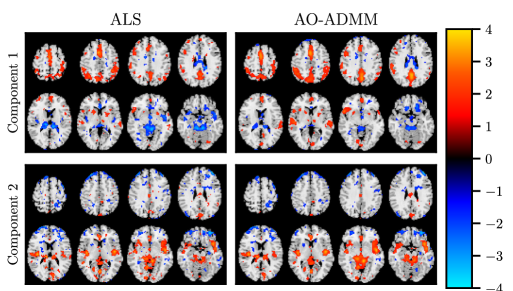

For neuroimaging applications, our motivation for imposing constraints on PARAFAC2 components is to improve their interpretability. Previous work has shown that PARAFAC2 can reveal dynamic networks (spatial dynamics) from fMRI data arranged as a subjects by voxels by time windows tensor [18]. However, the model is prone to noise affecting the extracted networks (see \creffig:fmri). To investigate if smoothness inducing regularization can improve interpretability, we used images from the MCIC collection [59], which contains fMRI-scans from healthy controls and patients with schizophrenia. We used the sensory motor (SM) task data, with the same feature extraction and preprocessing as [18].

We analyzed the fMRI data tensor using both regularized PARAFAC2 fitted with AO-ADMM and unregularized PARAFAC2 fitted with ALS, both ran for at most 8000 iterations. The , and factor matrices represented the subject-mode, voxel-mode and time-mode components, respectively. This configuration allows the voxel-mode components that indicate activation networks to evolve over time. To reduce the noise in the components, we chose a graph Laplacian regularizer based on the image gradient, thus penalizing large differences in neighboring voxels. We imposed ridge regularization on and to resolve the scaling indeterminacy, and non-negativity constraints on to resolve the sign indeterminacy.

The spatial regularizer encourages similar activation for neighboring voxels, which is a reasonable assumption for fMRI images [60]. Specifically, we used graph Laplacian regularization where if voxel and are neighboring voxels (in the von Neumann sense) and otherwise. The proximal operator of this penalty function involves solving a large linear system, similar to that obtained when solving Helmholtz’ equation with a finite difference scheme. To solve this system, we, therefore, used the conjugate gradient method, with a smoothed aggregation preconditioner, setting the near-nullspace component to a vector consisting only of ones.

We fixed the ridge penalty to , and performed a grid-search for the optimal smoothness penalty. The selected regularization parameter, , provided the strongest smoothing-effect while also not deteriorating the interpretability of the model.

fig:fmri shows a comparison of the unregularized and the regularized model. We see that imposing regularization yields smoother, more interpretable, components. The regularized sensorimotor component (i.e., component 1) shows the same significantly stronger activation in healthy controls compared to patients as the unregularized component (the -values obtained using a two-sample t-test on the corresponding subject-mode component vector is for AO-ADMM and for ALS) while the regions of activation are less affected by noise, and thus the interpretation is clearer.